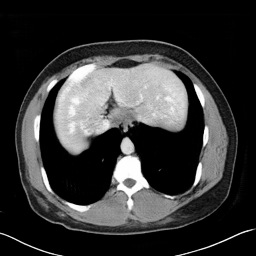

In many clinical settings, the use of both Computed Tomography (CT) and Magnetic Resonance (MRI) is necessary to pursue a thorough understanding of the patient's anatomy and to plan a suitable therapeutical strategy; this is often the case in MRI-based radiotherapy, where CT is always necessary to prepare the dose delivery, as it provides the essential information about the radiation absorption properties of the tissues. Sometimes, MRI is preferred to contour the target volumes. However, this approach is often not the most efficient, as it is more expensive, time-consuming and, most importantly, stressful for the patients. To overcome this issue, in this work, we analyse the capabilities of different configurations of Deep Learning models to generate synthetic CT scans from MRI, leveraging the power of Generative Adversarial Networks (GANs) and, in particular, the CycleGAN architecture, capable of working in an unsupervised manner and without paired images, which were not available. Several CycleGAN models were trained unsupervised to generate CT scans from different MRI modalities with and without contrast agents. To overcome the problem of not having a ground truth, distribution-based metrics were used to assess the model's performance quantitatively, together with a qualitative evaluation where physicians were asked to differentiate between real and synthetic images to understand how realistic the generated images were. The results show how, depending on the input modalities, the models can have very different performances; however, models with the best quantitative results, according to the distribution-based metrics used, can generate very difficult images to distinguish from the real ones, even for physicians, demonstrating the approach's potential.